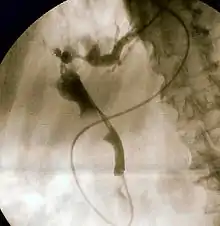

The gold standard test for biliary obstruction is still endoscopic retrograde cholangiopancreatography (ERCP). This involves the use of endoscopy (passing a tube through the mouth into the esophagus, stomach and thence to the duodenum) to pass a small cannula into the bile duct. At that point, radiocontrast is injected to opacify the duct, and X-rays are taken to get a visual impression of the biliary system. On the endoscopic image of the ampulla, one can sometimes see a protuberant ampulla from an impacted gallstone in the common bile duct or the frank extrusion of pus from the common bile duct orifice. On the X-ray images (known as cholangiograms), gallstones are visible as non-opacified areas in the contour of the duct. For diagnostic purposes, ERCP has now generally been replaced by MRCP. ERCP is only used first-line in critically ill patients in whom delay for diagnostic tests is not acceptable; however, if the index of suspicion for cholangitis is high, an ERCP is typically done to achieve drainage of the obstructed common bile duct.[7]